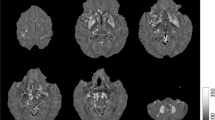

The T1-weighted images were used to segment the bilateral nucleus accumbens, caudate nucleus, putamen, globus pallidus, hippocampus, amygdala, and thalamus in an automated workflow based on the FIRST function of the FSL (created by the Analysis Group, FMRIB, Oxford, UK) (Fig. 1A). The SN, RN, and DN were manually segmented by a neurologist (M.K.) based on QSM (Fig. 1B). This was repeated by the same person 6 months later, and the consistency between the two manual segmentations was verified based on intraclass correlation coefficients, which were over 0.86 for all areas (0.992, left SN; 0.869, right SN; 0.998, left RN; 0.999, right RN; 0.999, left DN; and 1.000, right DN).

(A) Segmentation of the regions of interest (ROIs) in the deep brain structures of a representative volunteer by FSL. Illustrated are three-dimensional rendering of the ROI masks with automatic segmentation from FSL (a), and axial (b), coronal (c), and sagittal (d) plane views on the T1-weighted images. (B) Segmentation of the manually drawn ROIs of SN, RN, and DN. Abbreviations. Cd, caudate nucleus; Put, putamen; Gp, globus pallidus; Thal, thalamus; NAc, nucleus accumbens; R/L HP, right/left hippocampus; R/L Amg, right/left amygdala; SN, substantia nigra; RN, red nucleus; DN, dentate nucleus